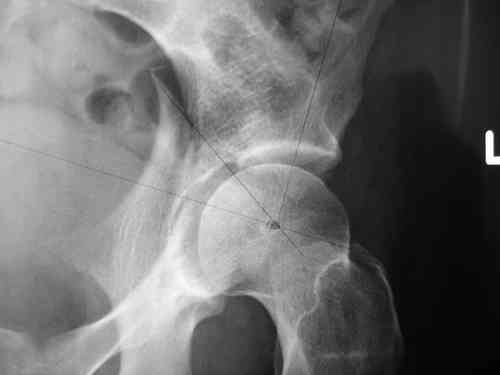

прилагаю пример с такой же давностью травмы, репонировали аппаратом

> в аппарате или одномоментно открыто. Лично я склоняюсь к аппаратному лечению на первом этапе.

задача непростая, если мало опыта в этом деле, подумайте еще раз